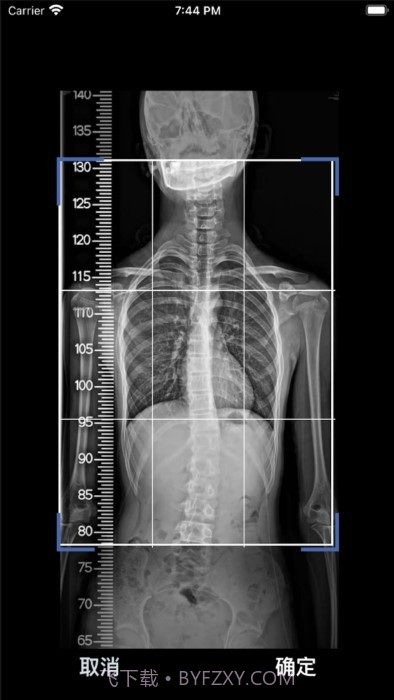

这款cobb角测量分析平台简直是医生和脊柱侧弯患者的福音!🌟 通过智能测量功能,能够迅速获取cobb角,准确率高得让人放心。对于有脊柱健康需求的小伙伴们来说,了解自己的状况特别重要,不仅能省时省力,更能随时存储和导出数据,后续分析也是轻松搞定!总之,这款应用为提高医疗效率、帮助患者掌握健康状况提供了强有力的支持,真心推荐给大家!

编辑点评:cobb角测量分析平台作为系统工具,这个应用的AI算法真的是一绝,相比其他同类工具更智能!,值得推荐。